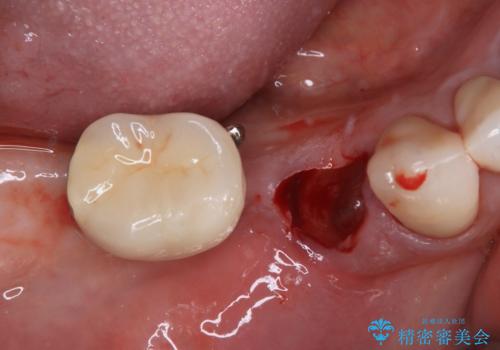

そのため、当院に新しく導入した手法により、抜歯をした日にインプラントを埋入し、そのままを仮歯を装着することで、他の歯への負担を軽減する計画を立てました。

インプラント埋入時に植立具合の安定性を測定したところ、十分な数値が得られたため、速やかに仮歯を装着して咬合回復をさせることができました。

抜歯を含めた外科処置を1回に抑えることができ、あっという間に治療を終えることができました。